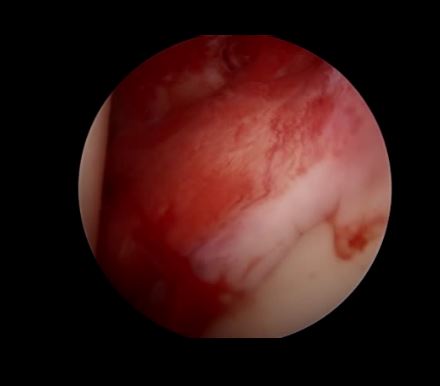

炎性肩关节——充血——滑膜炎

关节镜下可以彻底的清理关节内炎性滑膜组织及黏连带(盂肱关节及肩峰下关节)